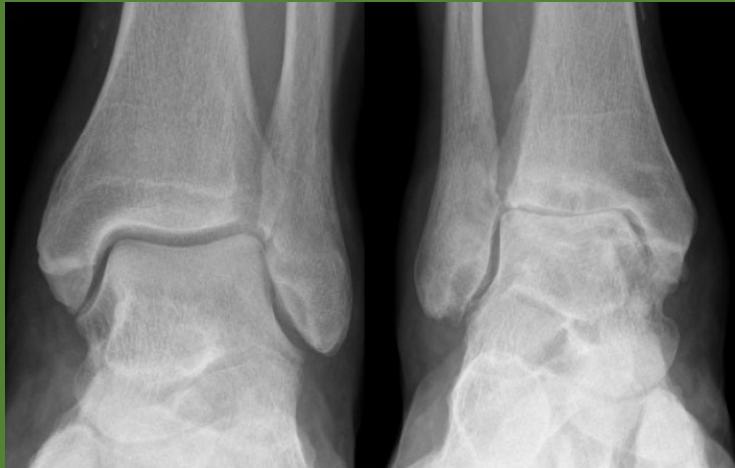

| Compartment Syndrome | Increased pressure within a closed fascial compartment, leading to reduced tissue perfusion, hypoxia, and irreversible muscle and nerve damage. Causes: Fractures (especially tibia/forearm), severe soft tissue trauma, arterial injury, burns, tight casts/dressings, post-ischemic reperfusion swelling, IV fluid extravasation, and bleeding disorders (e.g., hemophilia). High-Risk Notes: Pain may be absent in altered consciousness, children (monitor analgesia response), polytrauma, sedated/epidural cases, or concomitant nerve damage. Open fractures do not always decompress pressure. Gross/Clinical: -tense, shiny leg swelling with blisters in compartment syndrome.Imaging: - Intraoperative fasciotomy | History/Symptoms: Pain out of proportion to the injury (e.g., a “bursting” sensation), which is not relieved by analgesia. Clinical Features (The 5 P’s): - Pain with passive stretch (early, key sign; e.g., ankle dorsiflexion for leg, wrist for forearm). - Paresthesia (early). - Palpable tense swelling (shiny skin, blisters: clear=mild, serosanguinous=severe, bloody=worst; dusky/pallor skin). - Pallor, Paralysis, Pulselessness (late, ominous signs; pulses often palpable until late). Investigations: Primarily a clinical diagnosis (high suspicion key). Compartment pressure measurement can confirm: absolute pressure >30 mmHg or Delta Pressure (Diastolic BP - Compartment P) ≤ 25 mmHg. | Initial: ABCs, supplemental oxygen. Remove all circumferential dressings, casts (bivalve to skin), and splints. Elevate the limb to heart level (not above; higher reduces inflow). Correct any hypotension. Surgical: Urgent Fasciotomy if no response within 1h or confirmed pressure (prophylactic in high-risk like major osteotomy). Release all compartments/skin with long incisions; debride necrotic muscle via 4C’s (early: pink/red, soft, contracts/bleeds on pinch; late: dark, firm, no response); preserve neurovascular. Wound open (bulky dressing/splint, VAC, or boot-lace gradual closure); repeated inspections x48h; coverage in 3-5 days (skin graft usual; flap if nerves/vessels/bone exposed). | Cellulitis, Deep Vein Thrombosis (DVT), Arterial occlusion, Severe soft tissue injury without compartment syndrome; equivocal cases in polytrauma. | Complications: Volkmann’s ischemic contracture (permanent deformity, weakness, sensory loss, chronic pain). Contraindications (Fasciotomy): Confirmed >48h (irreversible damage, high infection risk from dead tissue); crush injuries with already necrotic muscle. |